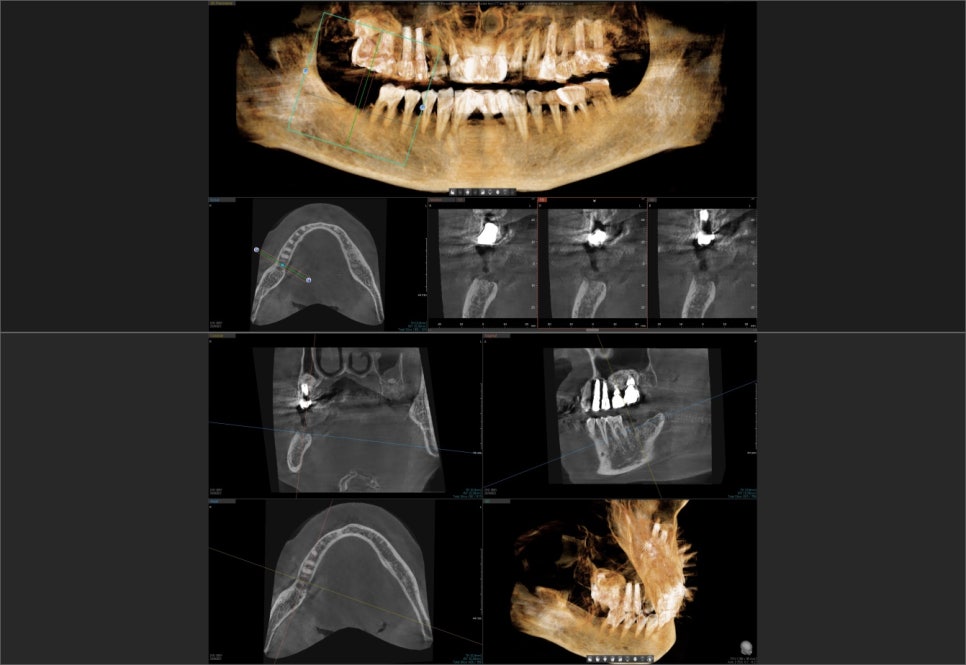

대치동 임플란트

위 엑스레이 사진과 같이 오른쪽 아래 어금니를 발치한 후 인공치근을 식립한 과정을 1차 수술이라고 합니다. 다른 부위에 식립한 임플란트와는 달리 치아의 뿌리에 해당하는 픽스쳐만 식립되어 있는 것을 확인할 수 있습니다. 이 인공치근이 잇몸뼈와 충분히 유착될 때까지 잇몸 아래 묻어두어서 안정적인 골유착을 유도합니다.

이 때 환자분의 잇몸뼈 상태나 식립한 임플란트 픽스쳐의 초기 고정 상태 등을 고려합니다. 환자의 잇몸뼈의 상태가 좋지 않거나 감염이 우려되는 경우, 또는 픽스쳐의 초기 고정력이 약한 경우, 어떠한 외부의 자극이 가해지지 않도록 커버 스크류라고 하는 작은 나사 뚜껑을 덮어서 잇몸 안에 픽스쳐를 묻어두어 골유착이 일어날 때까지 충분히 기다립니다. 추후 보철물을 연결하기 위해 잇몸 안에 묻어둔 임플란트 픽스쳐를 외부로 노출시키는 과정이 필요한데 이 과정이 바로 2차 수술에 해당합니다.